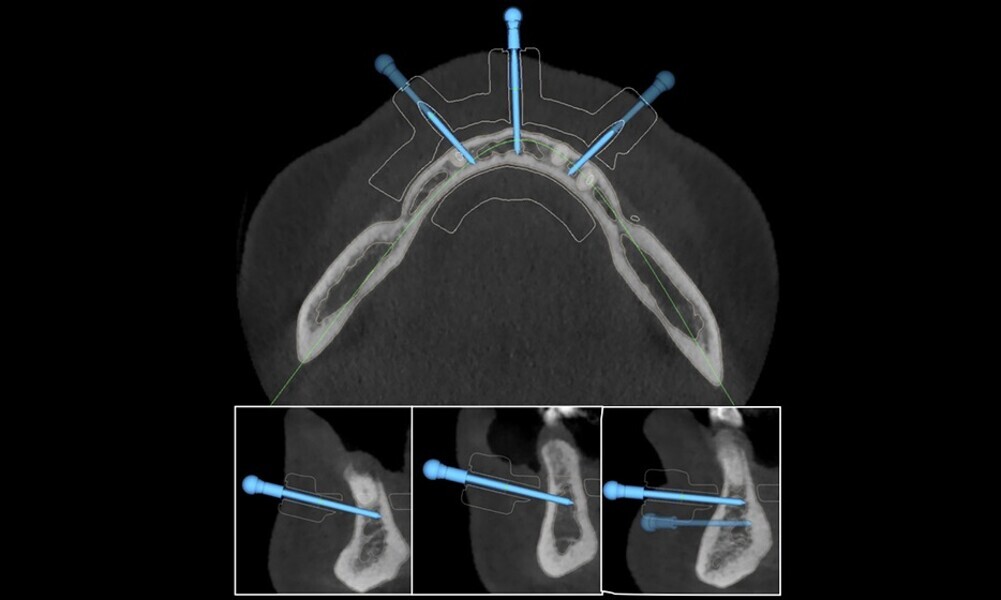

planning of implant positioning (18–21);

Figs. 16–28: The treatment workflow included the extraction of hopeless teeth, implant planning and positioning, and surgical guide fabrication.

Fig. 21